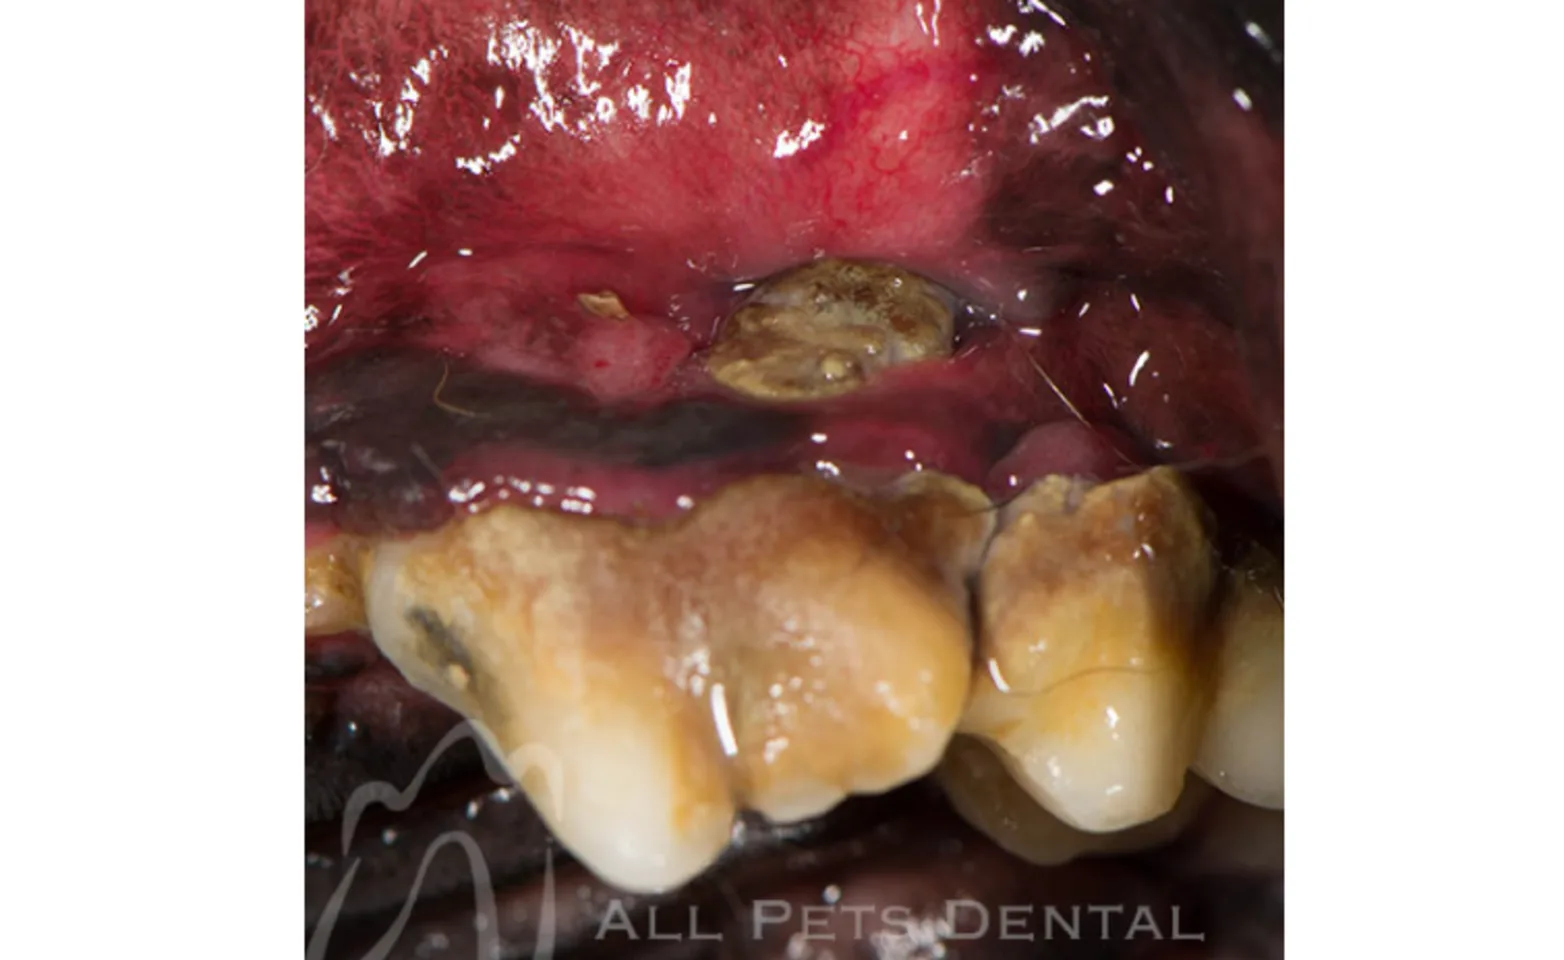

Stage 4

In stage 4 advanced periodontal disease, greater than half of the tooth's support is lost. Extraction is the treatment of choice to eliminate pain and inflammation.

Furcation Involvement

Furcation involvement is loss of the bone supporting the area where the tooth roots meet. Once furcation involvement is diagnosed, extraction is the treatment of choice.